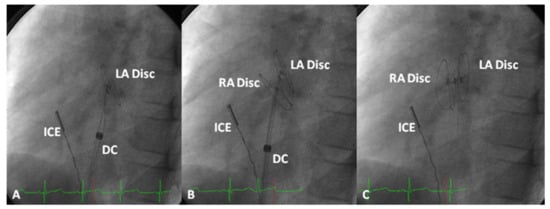

5.6. Type of Intervention